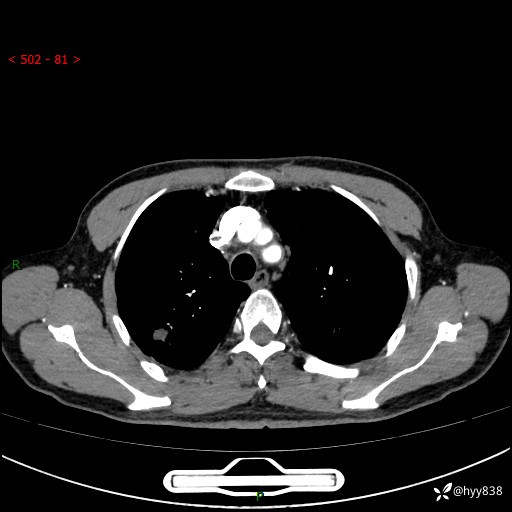

胸部CT平扫+增强